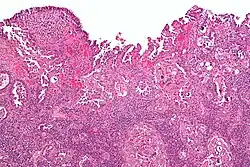

Histology H&E of uterine serous papillary carcinoma. H&E stain.

Histopathologically, uterine serous carcinomas is typically characterized by (1) nipple-shaped structures (papillae) with fibrovascular cores (2) marked nuclear atypia (irregularities in the nuclear membrane, enlarged nuclear size), (3) psammoma bodies and (4) cilia. These are general findings in serous tumors which are also seen in such tumors in other anatomic locations.